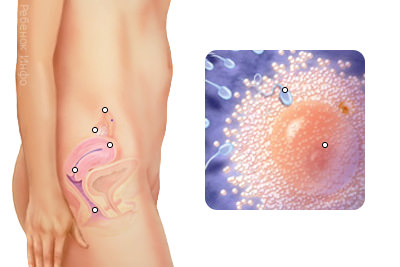

Акушери починають відлік вагітності від першого дня останньої менструації. У цей час вагітність фактично ще не настала, але організм жінки активно готується до цієї події. На 2 акушерської тижні вагітності жіночий організм створює всі умови для успішного зачаття: гормони готують відповідне середовище для розвитку плода, яйцеклітина дозріває і готується до запліднення. Діаметр яйцеклітини близько 0,1 мм, це найбільша клітина в організмі жінки, яка містить весь її генетичний набір. Після того як клітина повністю дозріває, починається її рух по фаллопієвій трубі до матки, де її повинен запліднити сперматозоїд. Процес запліднення, як правило, триває 3-6 годин, після чого яйце починає активно ділитися і приблизно через 7-8 днів закріплюється в матці жінки.

Говорити про те, як виглядає плід на 2 тижні ще рано, тому що його фактично не існує, в цей період тільки виникають передумови для його появи. Зараз це всього лише яйцеклітина, готова зустрітися зі сперматозоїдом і почати свій шлях в матку. На фото показаний процес овуляції.